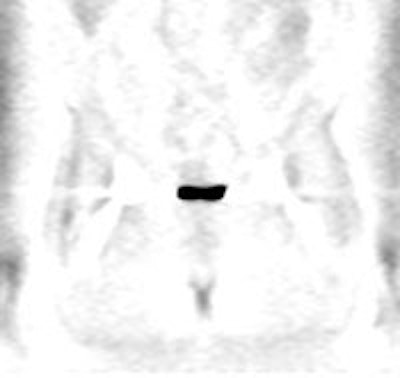

Normal vascular activity: Faint activity can be seen in the descending thoracic aorta (black arrows) |